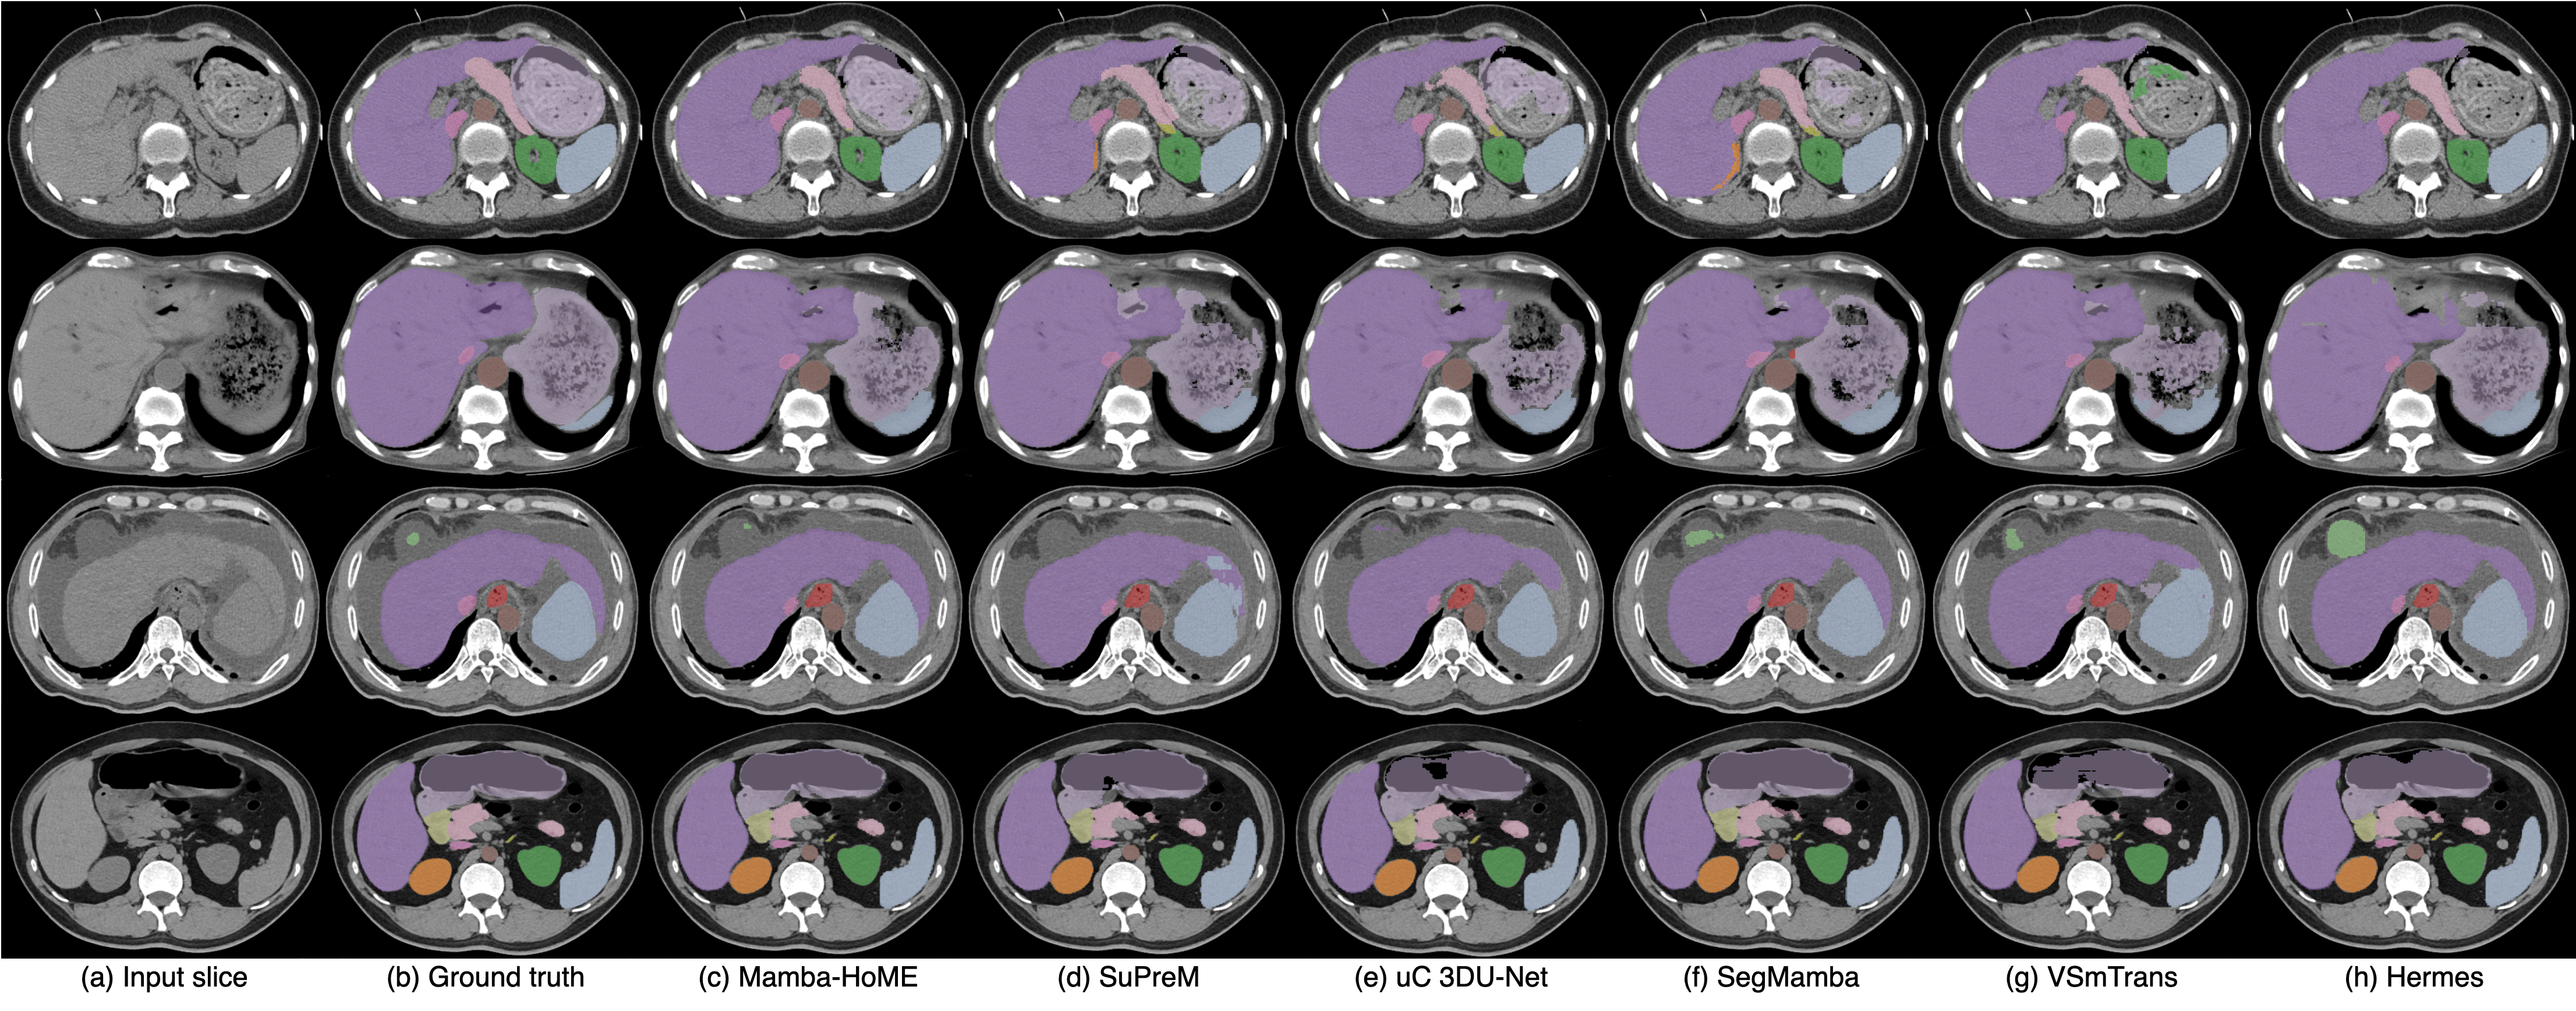

Qualitative results. Figure 2 presents a qualitative comparison of our proposed Mamba-HoME method against the five top-performing baselines across three primary 3D medical imaging modalities: CT, MRI, and US. These modalities exhibit different organ contrasts, noise levels, and resolutions. Mamba-HoME demonstrates consistent improvements in segmentation quality across these scenarios. In the first row, it effectively handles small and closely located structures, showing precise boundary delineation while reducing common artifacts seen in baseline predictions. The second row highlights its capability to accurately segment organs of various shapes and sizes, even under low image quality conditions, with reduced susceptibility to over- or under-segmentation. The third row illustrates Mamba-HoME’s robustness in handling noisy and low-resolution data, maintaining clear and anatomically accurate boundaries.

Figure 2: Qualitative segmentation results from top to bottom: CT, MRI, and 3D US. From left to right, each column shows the input slice, ground truth, the proposed Mamba-HoME, and the five next best-performing methods.

This adaptability highlights Mamba-HoME’s ability to mitigate challenges posed by variations in modality, resolution, and clinical context. Moreover, its consistently high performance across heterogeneous datasets underscores its potential for practical deployment, where robust, modality-agnostic feature representations and precise segmentation are essential for scalable, real-world medical imaging applications. As shown in Figure 3, supervised pre-training significantly improves Mamba-HoME’s performance compared to training from scratch or baseline methods, reducing artifacts and enhancing boundary segmentation for objects of varying sizes across the three primary 3D medical imaging modalities.

Figure 3: Qualitative segmentation results from top to bottom: CT, MRI, and 3D US. From left to right, each column shows the input slice, ground truth, our proposed pre-trained Mamba-HoME, Mamba-HoME trained from scratch, and the baseline SegMamba.